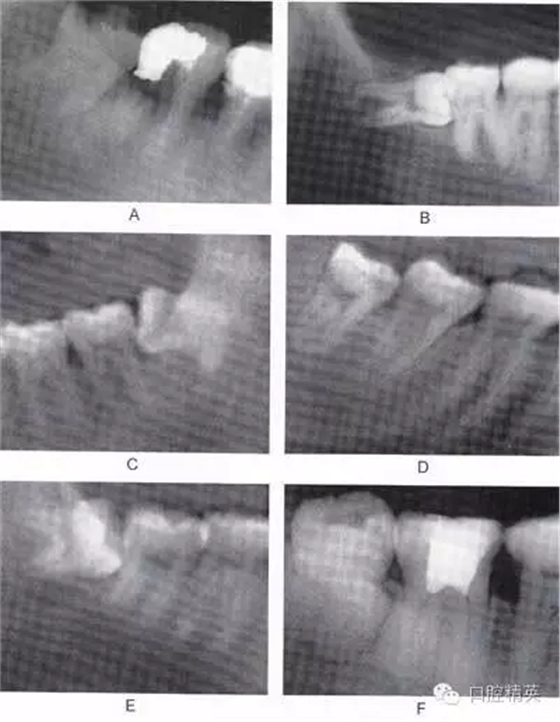

圖6-2 根據(jù)阻生牙相對(duì)于下頜升支前緣位置關(guān)系分為:第1類(lèi) (圖A):下頜升支前緣和第二磨牙遠(yuǎn)中面之間有足夠的間隙容 納第三磨牙牙冠;第2類(lèi)(圖B):約一半的第三磨牙牙冠被下 頜升支前緣覆蓋;第3類(lèi)(圖C):第三磨牙全部位于下頜升支 前緣內(nèi)

圖6-3 相對(duì)于聆平面的位置關(guān)系分為:A分類(lèi)(圖A):第三磨牙殆面平齊于第二磨牙聆面;B分類(lèi)(圖B):第三磨牙(牙合)面 位于第二磨牙殆面和牙頸部平面之間;C分類(lèi)(圖C):第三磨牙(牙合)面低于第二磨牙的牙頸部平面。一般情況下,近中阻生拔除難度比垂直阻生小,垂直阻生比水平阻生小,水平阻生比遠(yuǎn) 中阻生小;第1類(lèi)比第2類(lèi)簡(jiǎn)單,第2類(lèi)比第3類(lèi)簡(jiǎn)單;A分類(lèi)比B分類(lèi)簡(jiǎn)單,B分類(lèi)比C分類(lèi)簡(jiǎn)單。另外拔牙難度與牙齒形態(tài)、 患者年齡、牙周骨質(zhì)密度以及與下牙槽神經(jīng)管的關(guān)系也有關(guān)聯(lián)。 骨質(zhì)密度越大,年齡越大,患牙牙周骨質(zhì)鈣化程度越高,越難拔除.

圖6-4 以上類(lèi)型的下頜第三磨牙由于根阻力大,一般需要分根才能拔除

A.多根牙 B。超長(zhǎng)根 C。牙根向遠(yuǎn)中彎曲 D。兩根環(huán)抱 E。根分叉大 F,根端肥大 G。彎根 H.U型根(X線片及離體牙)